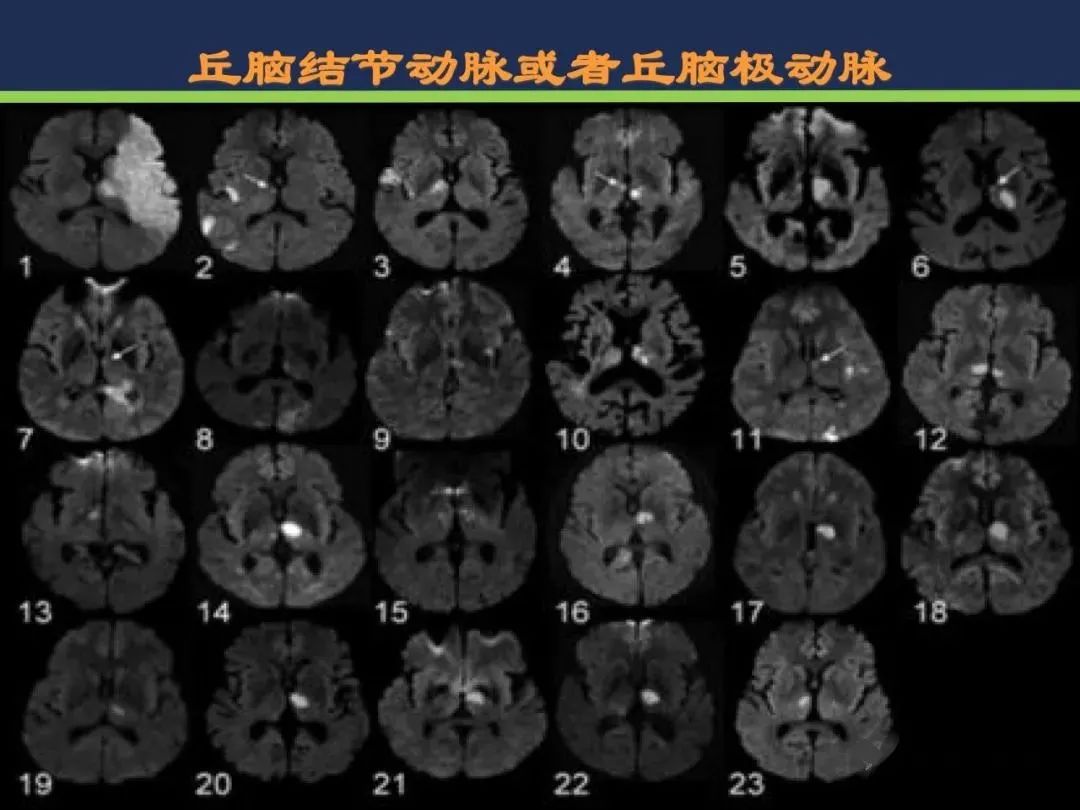

丘脑结节动脉